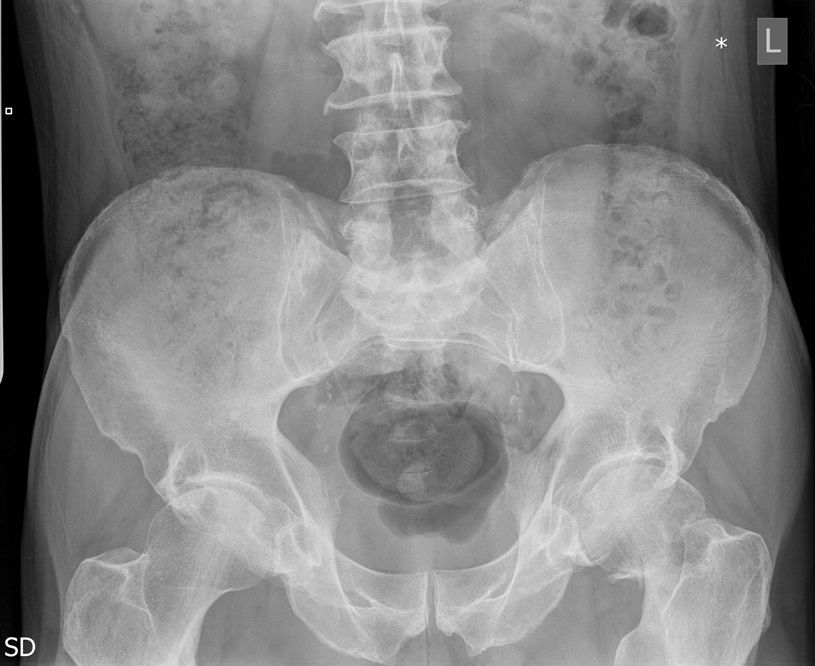

Question 1

Question

Which operation would you chose?

Answer

• THR

• Hemiarthroplasty